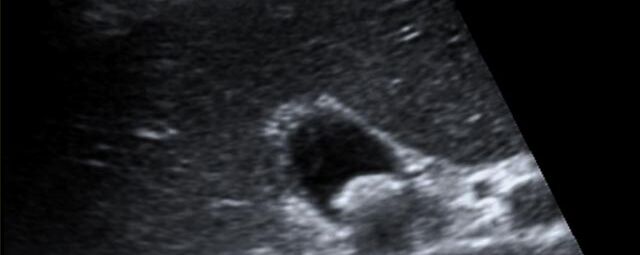

Die Sonographie ist ein bildgebendes Verfahren in der medizinischen Diagnostik, das mit Ultraschallwellen arbeitet. Ultraschall ist Schall mit einer Frequenz oberhalb der menschlichen Hörgrenze. Im medizinischen Bereich werden je nach Körperregion Ultraschallwellen in einem Frequenzbereich von ca. 3,5 – 18 Mhz verwendet. Die körpernahe Ultraschallsonde sendet durch einen piezoelektrischen Effekt kurze Schallwellenimpulse in den Körper. Ultraschall-Gel stellt den Kontakt zwischen Sonde und Körper her. Je nach Gewebeart werden diese Schallwellen im Körper unterschiedlich stark reflektiert. Anhand des zurückgesendeten Schallmusters kann das Ultraschallgerät Schnittbilder berechnen, auf denen die Organe des Körpers nach krankhaften Veränderungen untersucht werden können.

Der Arzt bewegt den Schallkopf mit leichtem Druck in verschiedene Richtungen. Die zu untersuchenden Strukturen können somit aus verschiedenen Perspektiven betrachtet werden. Aussagekräftige Bilder werden festgehalten und digital archiviert, Strukturen oder Organe können zusätzlich vermessen werden. Ein kurzes Befundgespräch erfolgt direkt nach der Untersuchung. Ihr zuweisender Arzt erhält von uns schriftlich einen ausführlichen Befundbericht.